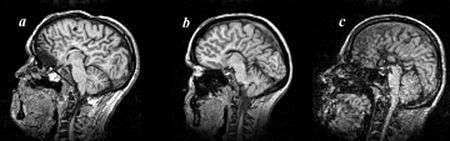

Colpocephaly is characterized by disproportionately large occipital horns of the lateral ventricles (also frontal and temporal ventricles in some cases). MRI and CT scans of patients demonstrate abnormally thick gray matter with thin poorly myelinated white matter. This happens as a result of partial or complete absence of the corpus callosum. Corpus callosum is the band of white matter connecting the two cerebral hemispheres. The corpus callosum plays an extremely important role in interhemispheric communication, thus lack of or absence of these neural fibers results in a number of disabilities.[7]

After birth, MR imaging can be done to look for cephalic abnormalities. This is the most commonly used method for diagnosing colpocephaly. Physicians look for abnormally large occipital horns of the lateral ventricles and diminished thickness of white matter.[7] Spinal tapping is not a preferred method for diagnosis because newborn babies with colpocephaly or hydrocephaly have open fontanelles which makes it difficult to collect CSF. Also, colpocephaly is not associated with increased pressure.[9]